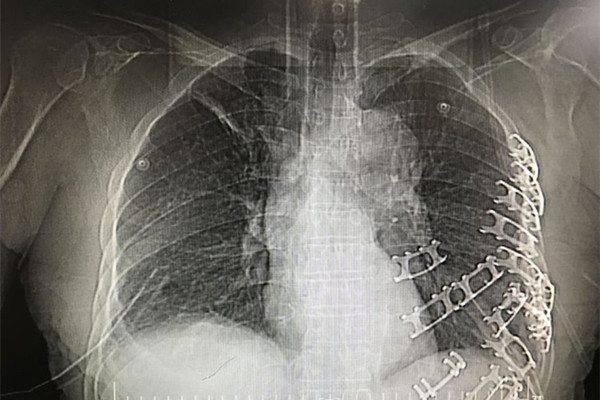

患者胸腹部挤压伤并创伤性窒息,病情极其危重,随时都会有生命危险,容不得半点耽搁。在对患者病情与手术方案进行细致的讨论后,由我院胸外科、创伤骨科、普外科、手麻科等科室专家组成的医疗团队立即对患者进行急诊手术抢救。胸外组经胸腔镜辅助行双侧胸腔探查见左侧4-12肋骨骨折,其中4-10肋骨成粉碎性骨折,左肺下叶广泛挫裂伤,胸腔积血2000余毫升,双侧膈肌破裂、肝脏完全疝入右侧胸腔。普外组探查腹腔积血1000余毫升、脾脏破裂。创伤骨科组探查见左上肢粉碎性骨折,软组织毁损严重,在多学科协作下成功完成左侧血胸清除、肺修补、左侧膈肌修补、左侧肋骨骨折复位内固定术等手术。各学科争分夺秒,配合默契,凭借着娴熟的医疗技术和丰富的临床经验,让奄奄一息的患者重获新生。